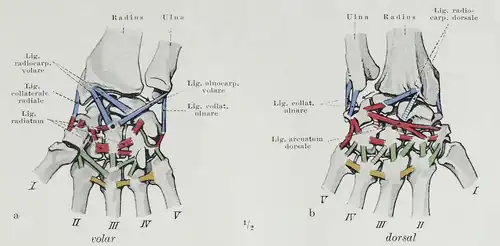

Ligaments

There are four groups of ligaments in the region of the wrist:[8]

- The ligaments of the wrist proper which unite the ulna and radius with the carpus: the ulnar and radial collateral ligaments; the palmar and dorsal radiocarpal ligaments; and the palmar ulnocarpal ligament. (Shown in blue in the figure.)

- The ligaments of the intercarpal articulations which unite the carpal bones with one another: the radiate carpal ligament; the dorsal, palmar, and interosseous intercarpal ligaments; and the pisohamate ligament. (Shown in red in the figure.)

- The ligaments of the carpometacarpal articulations which unite the carpal bones with the metacarpal bones: the pisometacarpal ligament and the palmar and dorsal carpometacarpal ligaments. (Shown in green in the figure.)

- The ligaments of the intermetacarpal articulations which unite the metacarpal bones: the dorsal, interosseous, and palmar metacarpal ligaments. (Shown in yellow in the figure.)